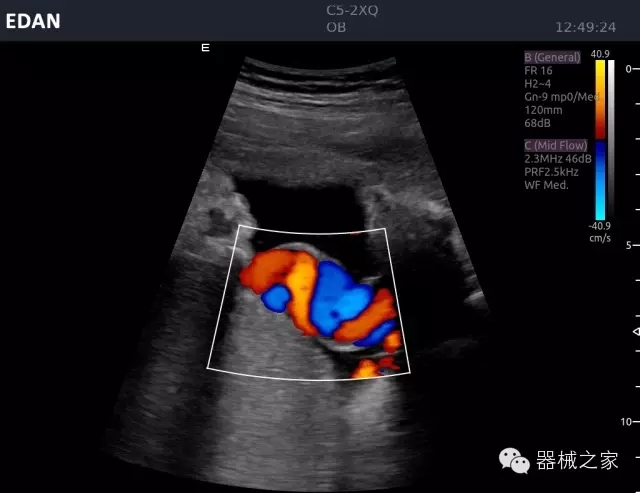

臨床圖片賞析

臍帶血流